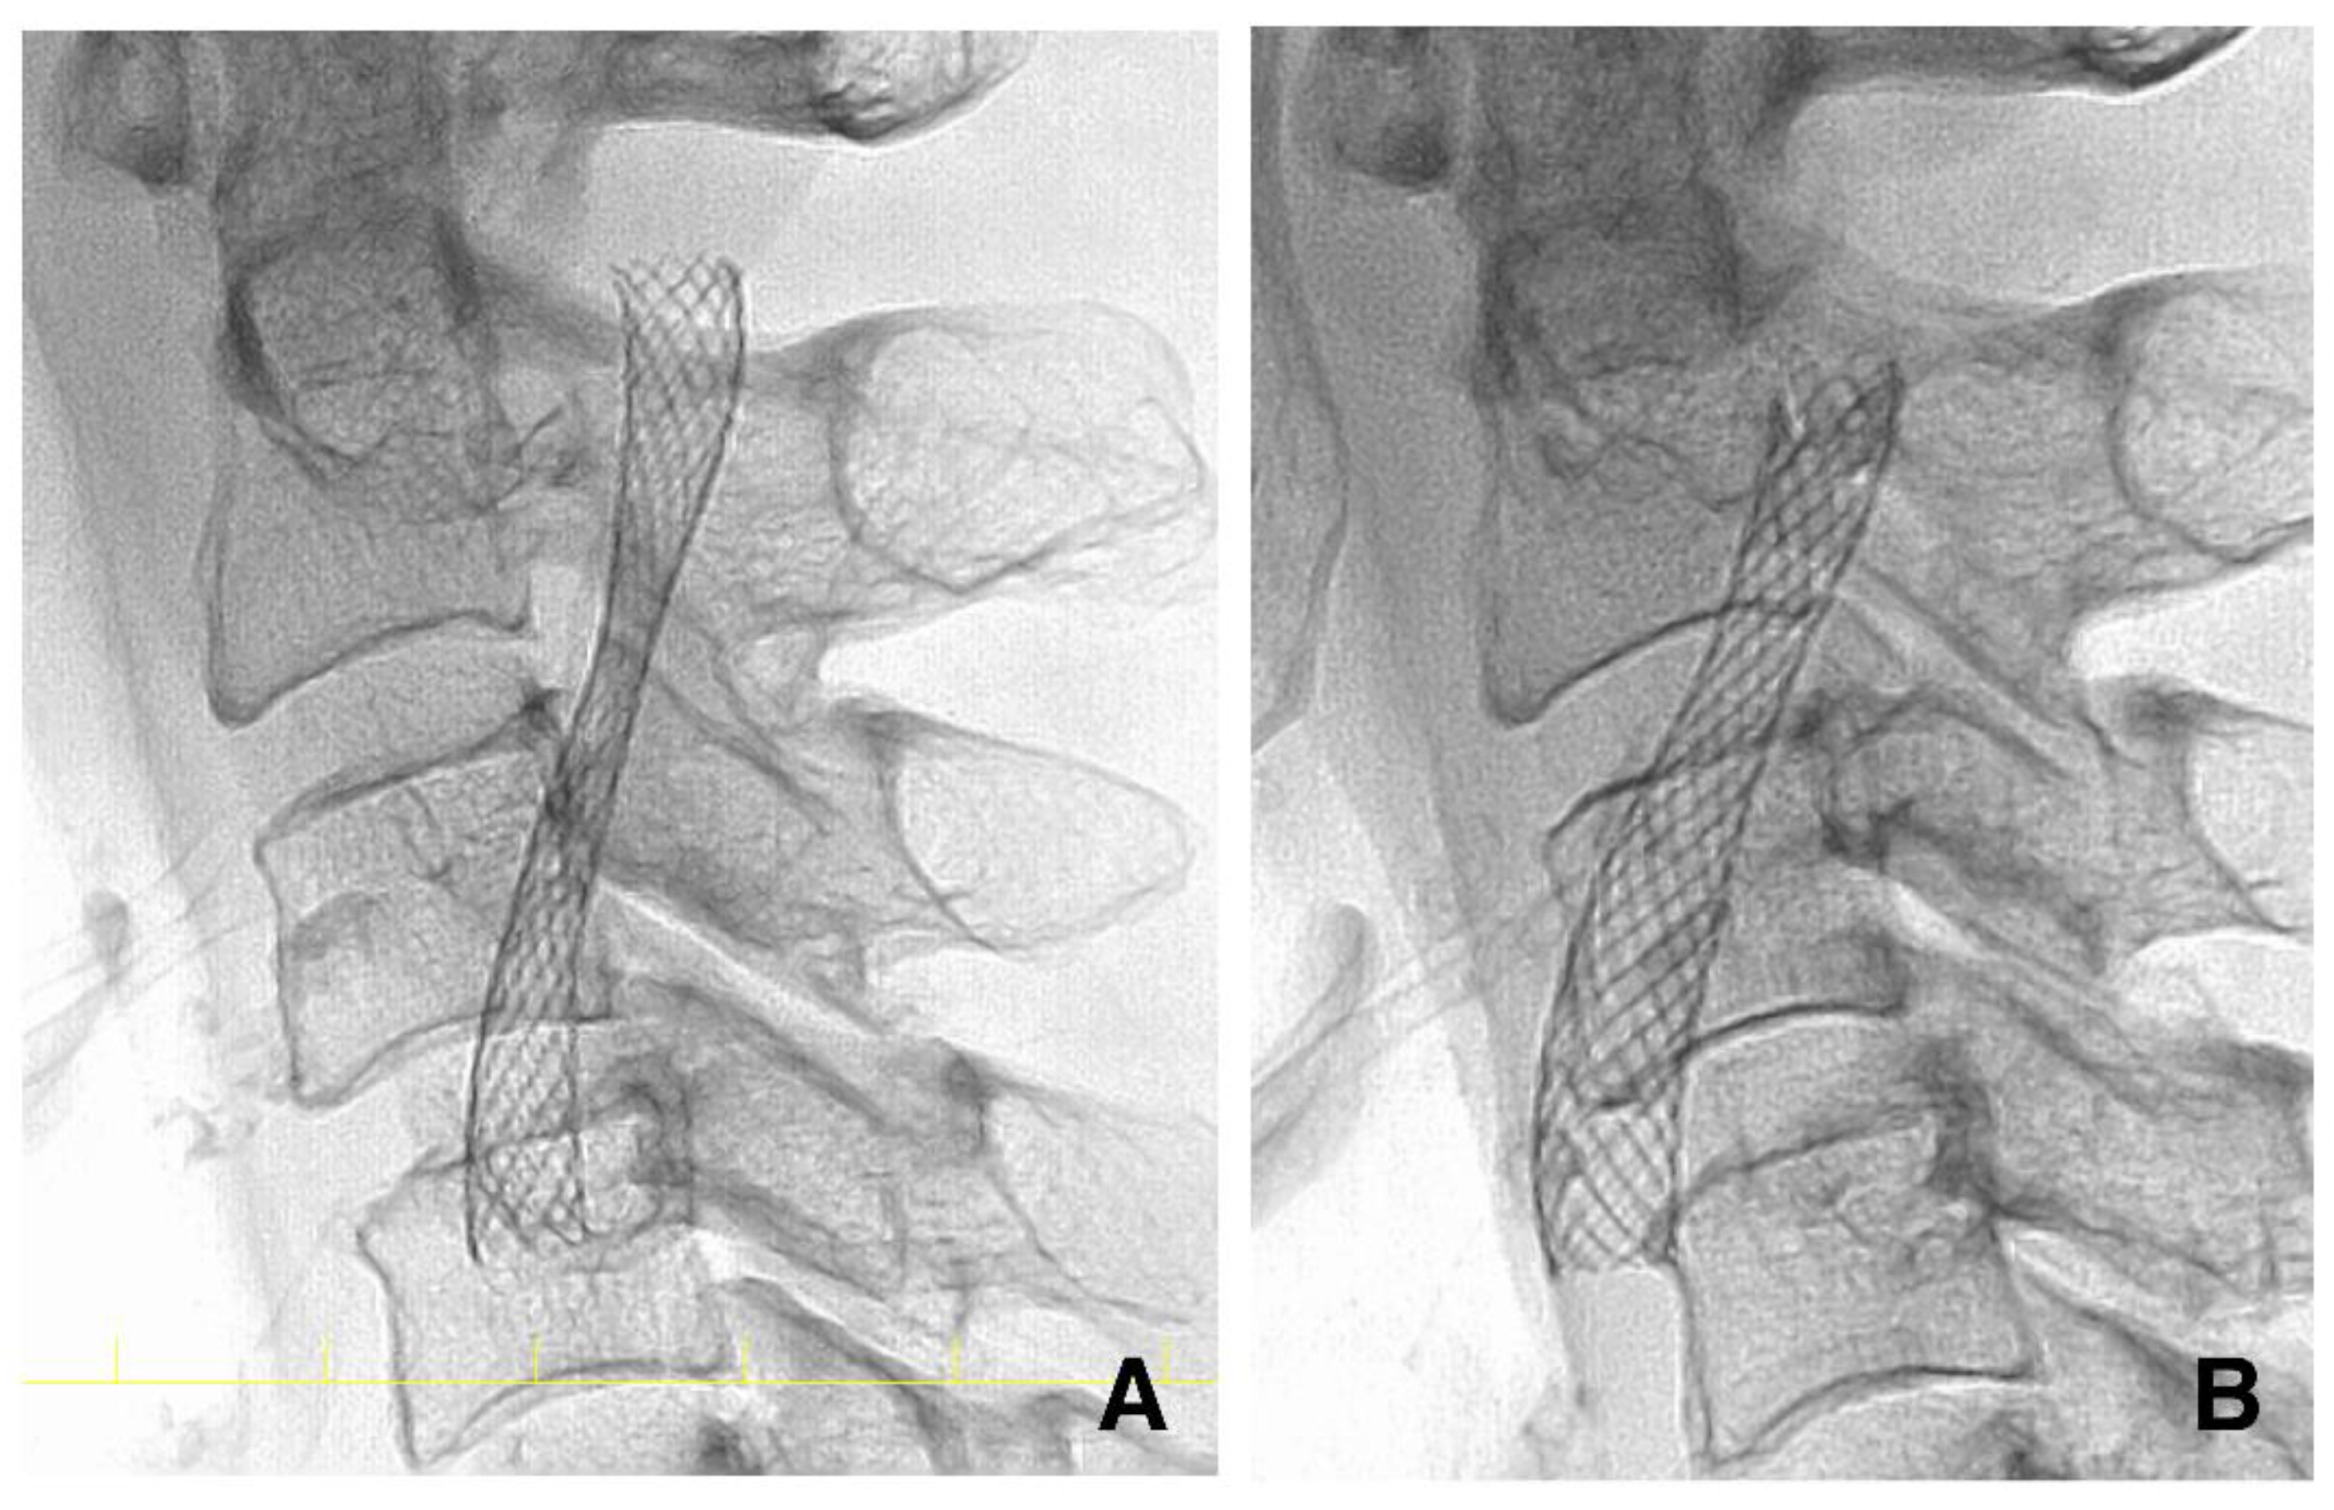

As reported previously, we expected the stent to self-expand over a few months. However, some stents fail to expand. Therefore, DSA was performed at four months (ranging from three to six months after CAS) to assess the stent diameter accurately, as reported in previous studies (Figure 3) [21,22]. Residual stenosis was defined as having an MSD < 3.0 mm at four months. The MSD was measured on the lateral view image immediately after and four months after CAS (Figure 4). When patients rejected DSA at four months, carotid ultrasonography was performed to measure the MSD.

Figure 4.

Pictures of the stent in the same case as in Figure 2. (A) The stent is stenotic immediately after carotid artery stenting. (B) The stent has expanded spontaneously at four months.